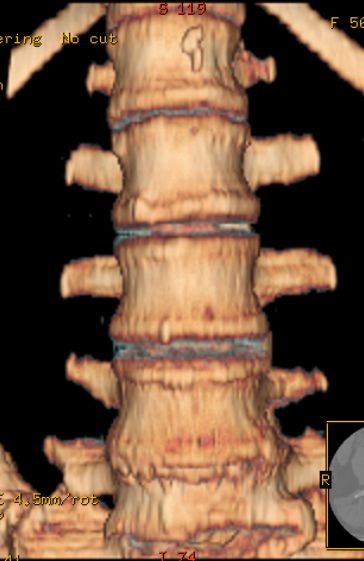

以下是引用余辉在2007-9-4 21:00:00的发言:[br]椎体棘突有点异常(像是被切割了),不知有否手术史,如椎体融合术等。单纯的退行性变可以出现椎间隙变窄,但同时一般会出现椎体上下缘的硬化增生,且椎体间完全融合的机率更小,本例椎体完全融合且椎体上下皮质缘破坏掉了,如果没有手术史,就应该考虑椎间盘炎性病变了,且椎体棘突及棘间韧带的变化也并不是不支持这个,多数小关节也融合了,且其形态也容易让人联想到如强脊炎及类风关等病变。[br][br][本贴已被 余辉 于 2007-9-4 21:03:55 修改过]

以下是引用chry3在2007-9-4 20:42:00的发言:[br]椎间盘病史?是什么样的病史,无双下肢放射痛,那就不是椎间盘突出了。是感染、什么性质的?[br]从图象看椎间隙消失,椎间盘组织未见,锥体滑脱是因为椎间盘溶解造成的[br]l4、5椎体骨质结构未见异常,l5上缘是l4的长期压迫所致[br]还是考虑椎间盘感染,结核。[br]